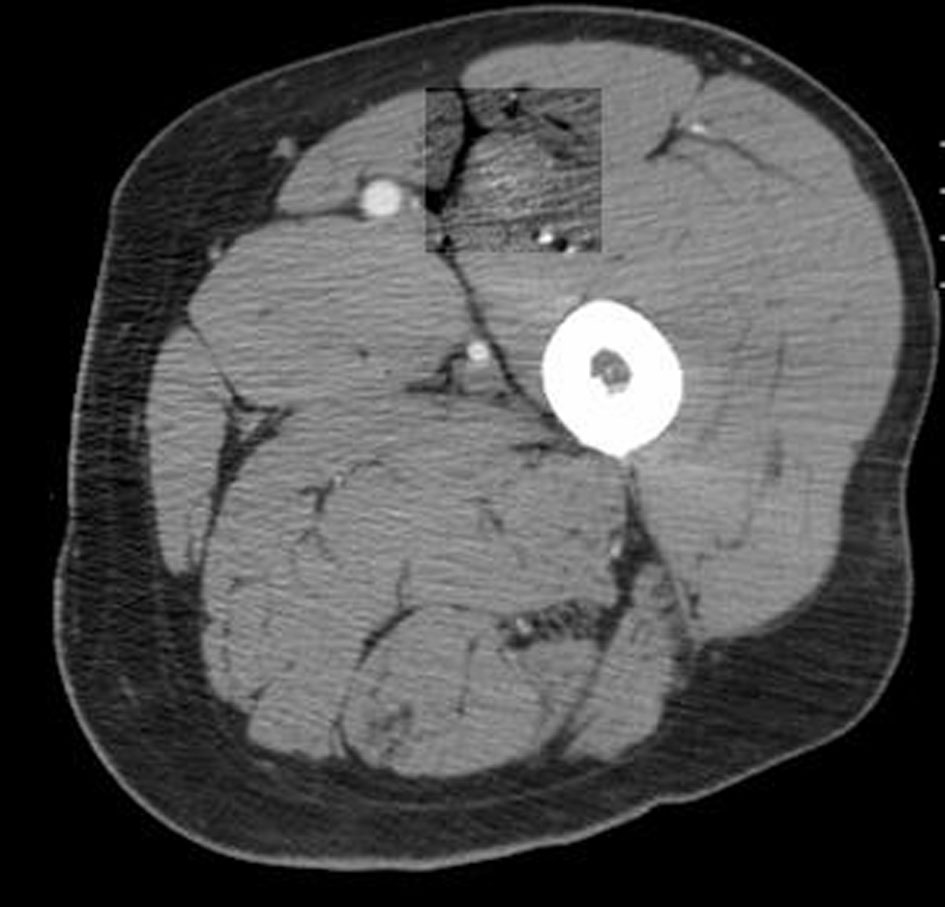

A 66-year-old male presented with small bowel obstruction due to a cecal mass requiring exploratory laparotomy. Pathology revealed a well-differentiated neuroendocrine tumor with regional nodal metastases (Figure 1 shows small intestinal tumor in low power view (a), high power view (b), chromogranin stain (c), synaptophysin stain (d)). Eight months after surgery the patient presented with persistent diarrhea. Indium 111 octreotide scintigraphy (OctreoScan®) revealed increased activity in the left leg and right lobe of the liver (Figure 2 with green arrow shows metastasis to the liver, red arrow showing metastasis to left thigh). An abdominal MRI demonstrated a 2 cm subcapsular lesion at the right hepatic lobe (Fig. 3) and CT scan demonstrated an enhancing soft tissue mass in the left vastus intermedius muscle measuring 30 × 17 × 16 mm (Fig. 4). Biopsy of the left thigh lesion showed metastatic well-differentiated neuroendocrine tumor (Fig. 5). Subsequent CT scan demonstrated increase in the size of the liver and muscular lesions and Sandostatin® LAR was initiated.

![]() Click for large image | Figure 4. CT scan of the left thigh. |